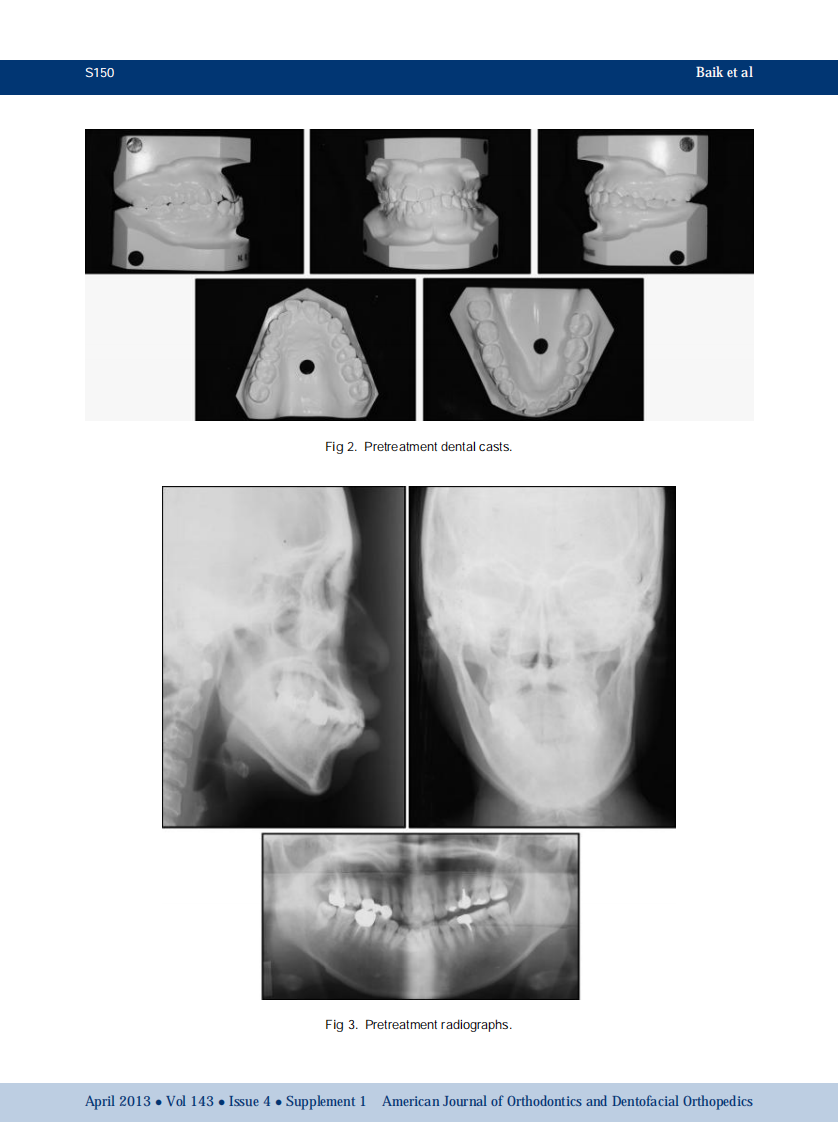

AJO-DO

1-s2.0-S0889540612009006-main.pdf